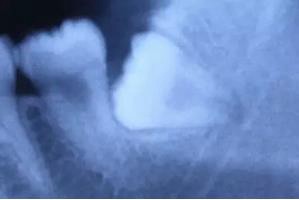

1、最不能理解的问题:智齿不疼,为什么要拔啊?

这恐怕是大家最不能理解的问题了吧,牙医也不是建议大家拔除所有智齿。只有下面情况,牙医才不建议拔除:智齿萌出完全,具有咬合功能,或者十二三岁的患者因为龋齿拔除了第一、或者第二磨牙的患者,智齿建议保留。

对于智齿已经出现过问题,或者将来可能出现问题的阻生智齿,牙医一般建议拔除。个人的解释是:阻生智齿是一颗颗肯定要爆炸的炸弹,只是牙医还不能预测什么时候会爆炸。对于牙医建议拔除的智齿,多多少少会存在一些问题,有的可能会出现智齿冠周炎、有的是会出现咬合创伤、有的会出现食物嵌塞、有的会导致邻牙出现龋齿,甚至是牙髓炎。所以对于可能要出现问题的阻生智齿,牙医建议预防性的拔除。